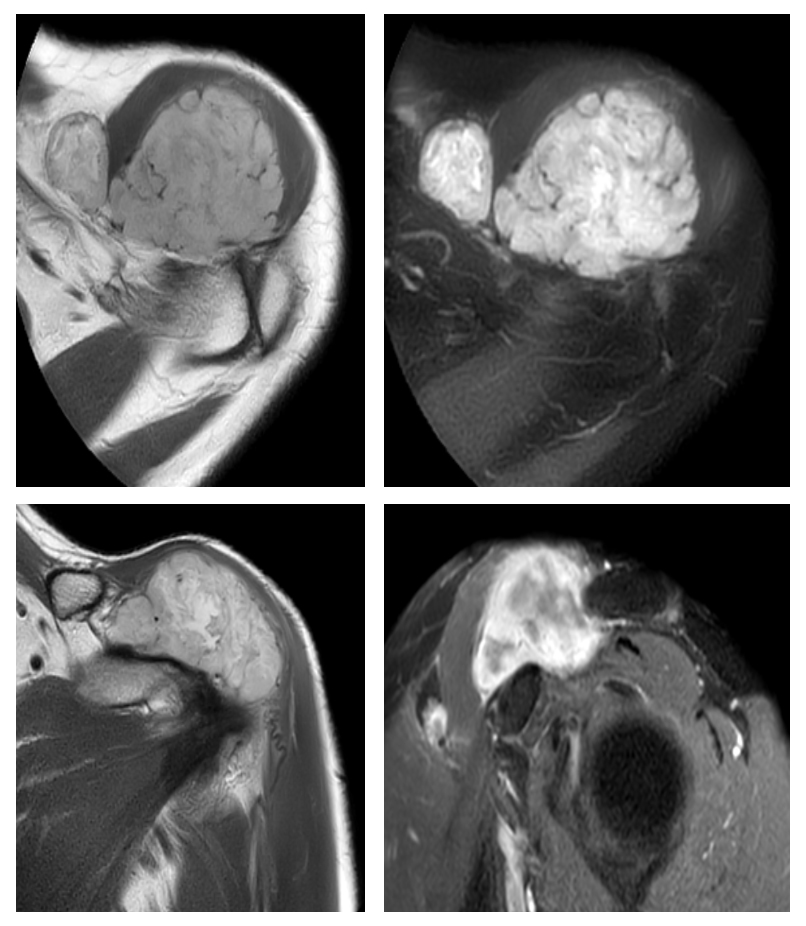

Ameliyat Öncesi: Omuz yerleşimli düzensiz sınırlı heterojen yumuşak doku tümörü görülmekte.